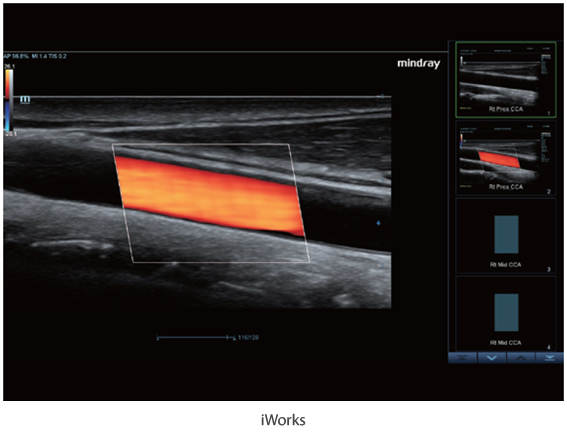

–ú–Ĺ–ĺ–≥–ĺ—Ą—É–Ĺ–ļ—Ü–ł–ĺ–Ĺ–į–Ľ—Ć–Ĺ–į—Ź —Ā–ł—Ā—ā–Ķ–ľ–į DC-60 Exp —Ā X-Insight –Ņ—Ä–Ķ–ī—Ā—ā–į–≤–Ľ—Ź–Ķ—ā —Ā–ĺ–Ī–ĺ–Ļ –ļ–ĺ–ľ–Ņ–Ľ–Ķ–ļ—Ā–Ĺ–ĺ–Ķ —Ä–Ķ—ą–Ķ–Ĺ–ł–Ķ, –ļ–ĺ—ā–ĺ—Ä–ĺ–Ķ –Ņ–ĺ–ľ–ĺ–≥–į–Ķ—ā —É–Ņ—Ä–į–≤–Ľ—Ź—ā—Ć –Ņ–ĺ–≤—Ā–Ķ–ī–Ĺ–Ķ–≤–Ĺ–ĺ–Ļ –ļ–Ľ–ł–Ĺ–ł—á–Ķ—Ā–ļ–ĺ–Ļ –Ņ—Ä–į–ļ—ā–ł–ļ–ĺ–Ļ —Ā –Ľ–Ķ–≥–ļ–ĺ—Ā—ā—Ć—é –ł —É–≤–Ķ—Ä–Ķ–Ĺ–Ĺ–ĺ—Ā—ā—Ć—é.

–ě—Ā–Ĺ–ĺ–≤—č–≤–į—Ź—Ā—Ć –Ĺ–į –≥–Ľ—É–Ī–ĺ–ļ–ĺ–ľ –Ņ–ĺ–Ĺ–ł–ľ–į–Ĺ–ł–ł –Ņ–ĺ—ā—Ä–Ķ–Ī–Ĺ–ĺ—Ā—ā–Ķ–Ļ –ļ–Ľ–ł–Ķ–Ĺ—ā–ĺ–≤, –ļ–ĺ–ľ–Ņ–į–Ĺ–ł—Ź Mindray —Ä–į–∑—Ä–į–Ī–ĺ—ā–į–Ľ–į —Ā–ł—Ā—ā–Ķ–ľ—É DC-60 Exp —Ā X-Insight, —á—ā–ĺ–Ī—č –ĺ–Ī–Ķ—Ā–Ņ–Ķ—á–ł—ā—Ć –≤—č—Ā–ĺ–ļ—É—é –Ņ—Ä–ĺ–ł–∑–≤–ĺ–ī–ł—ā–Ķ–Ľ—Ć–Ĺ–ĺ—Ā—ā—Ć –ł —ā–ĺ—á–Ĺ–ĺ—Ā—ā—Ć –≤–ł–∑—É–į–Ľ–ł–∑–į—Ü–ł–ł –≤–ļ—É–Ņ–Ķ —Ā –Ĺ–į–≥–Ľ—Ź–ī–Ĺ–ĺ—Ā—ā—Ć—é, –ł—Ā–ļ–Ľ—é—á–ł—ā–Ķ–Ľ—Ć–Ĺ–ĺ–Ļ –ł–Ĺ—ā–Ķ–Ľ–Ľ–Ķ–ļ—ā—É–į–Ľ—Ć–Ĺ–ĺ—Ā—ā—Ć—é –ł –ĺ–≥—Ä–ĺ–ľ–Ĺ—č–ľ –ĺ–Ņ—č—ā–ĺ–ľ.